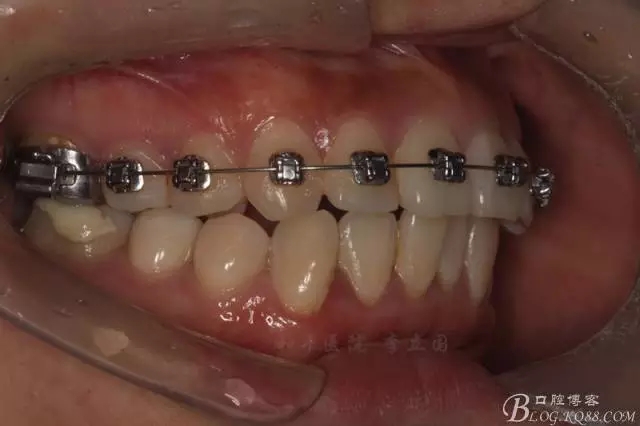

如圖,該病例為簡單排齊病例,但77鎖合是矯治中的關(guān)鍵所在,你會(huì)怎么處理?

該病例主要為17、27頰側(cè)位同時(shí)伴有伸長,當(dāng)然種植支抗可以解決,但還有簡單實(shí)用的辦法嗎?如圖,在橫腭桿遠(yuǎn)中延伸出牽引鉤,位置盡量遠(yuǎn)離合平面,7粘舌側(cè)扣,牽引力的方向?yàn)閴旱图吧嘞?,下圖為兩個(gè)月的效果,17已到位,27還未到位。